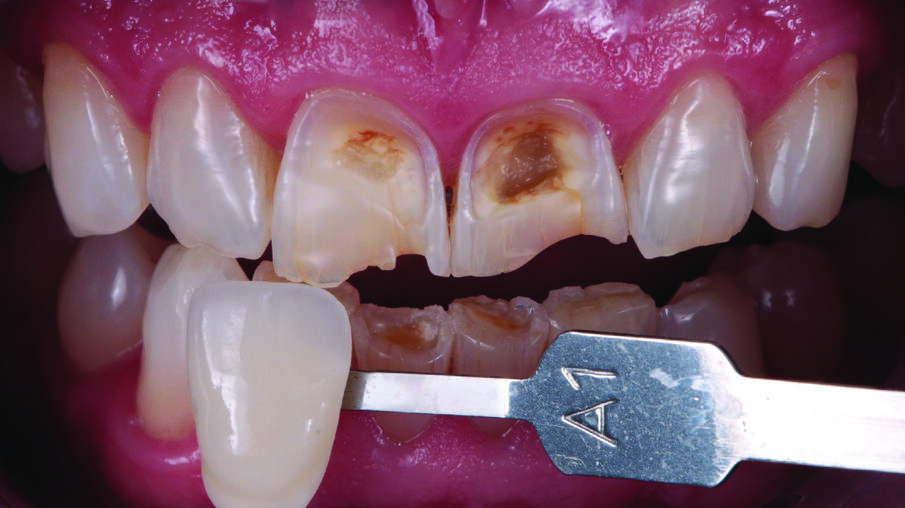

Tooth shade was determined with the aid of the VITA classical A1-D4® shade guide. The shade A1 matched the sound tooth structure. This corresponded with 3M™ Filtek™ Universal Restorative’s A1 shade.